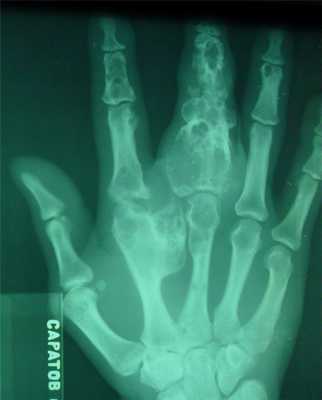

- поражаются фаланги, пястные, плюсневые, реже запястные кости, отростки позвонков, передние концы верхних ребер, тазовый скелет, грудина и весьма редко - длинные трубчатые периферические кости,

- в малых цилиндрических костях хондромы гнездятся в диафизах и эпифизах, в больших трубчатых - только в метафизарных костях,

- как правило хрящевые опухоли множественны и чаще всего наблюдаются в числе одного или нескольких на фалангах рук и пястных костях,

- чаще процесс двусторонний, но не симметричный.

- опухоли шарообразны или овальны, расположены то центрально и вздувают кость изнутри, то эксцентрично и более поверхностно и связаны только с корковым веществом кости,

- опухоль состоит из прозрачного, хрящевого фона на котором видны островки, точечки из извести или костного вещества,

- наружные контуры гладкие и при доброкачественном течении не прерываются,

- на месте слияния опухолевых шаров костная перегородка иногда толстая, в других случаях истончена или отсутствует,

- при поражении эпифизарных хрящей приходится видеть торможение роста кости в длину или ее искривлении,

- нередко центрально расположенная хондрома осложняется патологическим переломом,

- корковый слой неравномерен и местами утолщен,

- при хондроме поверхность кости шероховата.